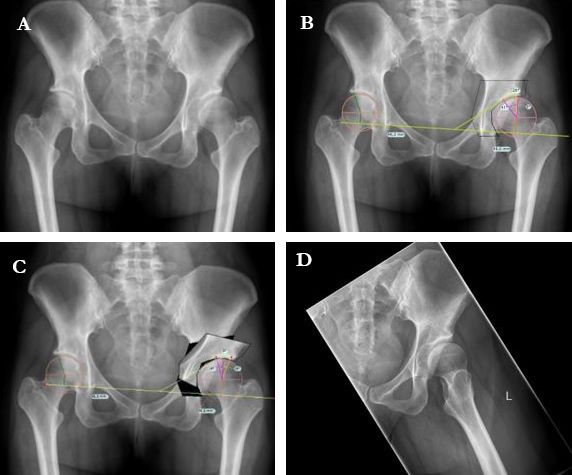

The radiological criteria for a DDH are currently defined as a lateral CE-angle of less than 23°. Other radiological markers are an acetabular index greater than 14° and a femur extrusion index greater than 27° 4. Prior to surgery the authors recommend a digital planning to determine the optimum amount of acetabular reorientation and avoid over- or under-correction (Fig. 1) in anteroposterior pelvic overview. This is done using the identical digital 2D planning software for arthroplasty procedures (TraumaCad, BrainLab, Munich). On the anteroposterior pelvic overview, a postoperative LCE angle of 30°, a positive acetabular index, a femoral extrusion index ≤ 25% and an anteverted acetabulum are the target values for correction.